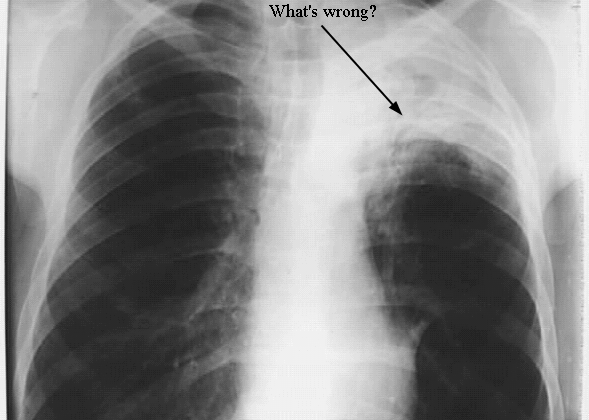

Thorax: Lung Cancer

Arrow: An unusual opacity in the left lung.